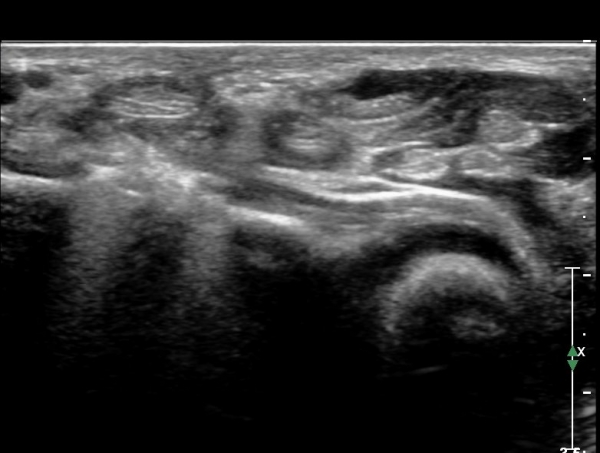

¾Æ·§ÆÈ »óºÎ Ⱦ´Ü¸é°Ë»ç¿¡¼­ Àü°ñ°£ ½Å°æ Áö¹è¸¦ ¹Þ´Â FPL, FDP ¿¡¼­ ½Å°æ¸¶ºñ ¼Ò°ß(°í¿¡ÄÚ ±ÙÀ§Ãà)À»

º¸ÀÌÁö ¾ÊÀ½(»çÁø 1)